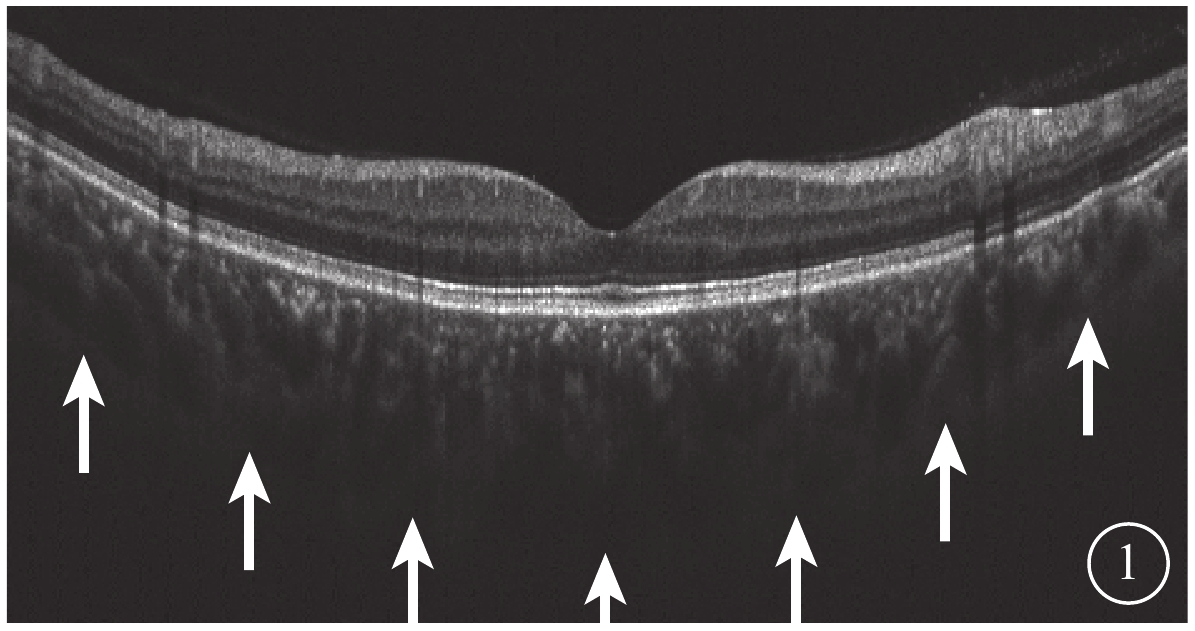

所有受檢者均于下午2:00~6:00行最佳矯正視力、屈光度、眼壓、裂隙燈顯微鏡、間接檢眼鏡、SS-OCT檢查和AL測量。采用德國Zeiss公司IOL-Master測量AL。采用日本Topcon公司Triton OCT儀以波長1050 nm,掃描速度100 000次/s對黃斑區進行掃描。黃斑區12.0 mm直徑行12條放射線SS-OCT掃描;黃斑區3.0 mm×3.0 mm行SS-OCTA掃描。由另一位未知研究對象分組的醫生選取圖像質量最高的一張SS-OCT圖像,測量黃斑中心凹下視網膜色素上皮層外界至鞏膜內界強反光線的垂直長度作為中心凹下脈絡膜厚度(SCT)(圖1)。截取Bruch膜下1/2脈絡膜厚度所在層面SS-OCTA圖像,使用Image J軟件將所得灰度圖按照文獻[10]的計算方法進行二值化處理得到黑白圖后,計算圖中黑色像素數占圖像總像素數的百分比,即為脈絡膜大血管層高速血流密度(FBFD)。

圖1

脈絡膜厚度測量示意圖。脈絡膜鞏膜交界面(白箭)

圖1

脈絡膜厚度測量示意圖。脈絡膜鞏膜交界面(白箭)

所有受檢者均于下午2:00~6:00行最佳矯正視力、屈光度、眼壓、裂隙燈顯微鏡、間接檢眼鏡、SS-OCT檢查和AL測量。采用德國Zeiss公司IOL-Master測量AL。采用日本Topcon公司Triton OCT儀以波長1050 nm,掃描速度100 000次/s對黃斑區進行掃描。黃斑區12.0 mm直徑行12條放射線SS-OCT掃描;黃斑區3.0 mm×3.0 mm行SS-OCTA掃描。由另一位未知研究對象分組的醫生選取圖像質量最高的一張SS-OCT圖像,測量黃斑中心凹下視網膜色素上皮層外界至鞏膜內界強反光線的垂直長度作為中心凹下脈絡膜厚度(SCT)(圖1)。截取Bruch膜下1/2脈絡膜厚度所在層面SS-OCTA圖像,使用Image J軟件將所得灰度圖按照文獻[10]的計算方法進行二值化處理得到黑白圖后,計算圖中黑色像素數占圖像總像素數的百分比,即為脈絡膜大血管層高速血流密度(FBFD)。

圖1

脈絡膜厚度測量示意圖。脈絡膜鞏膜交界面(白箭)

圖1

脈絡膜厚度測量示意圖。脈絡膜鞏膜交界面(白箭)